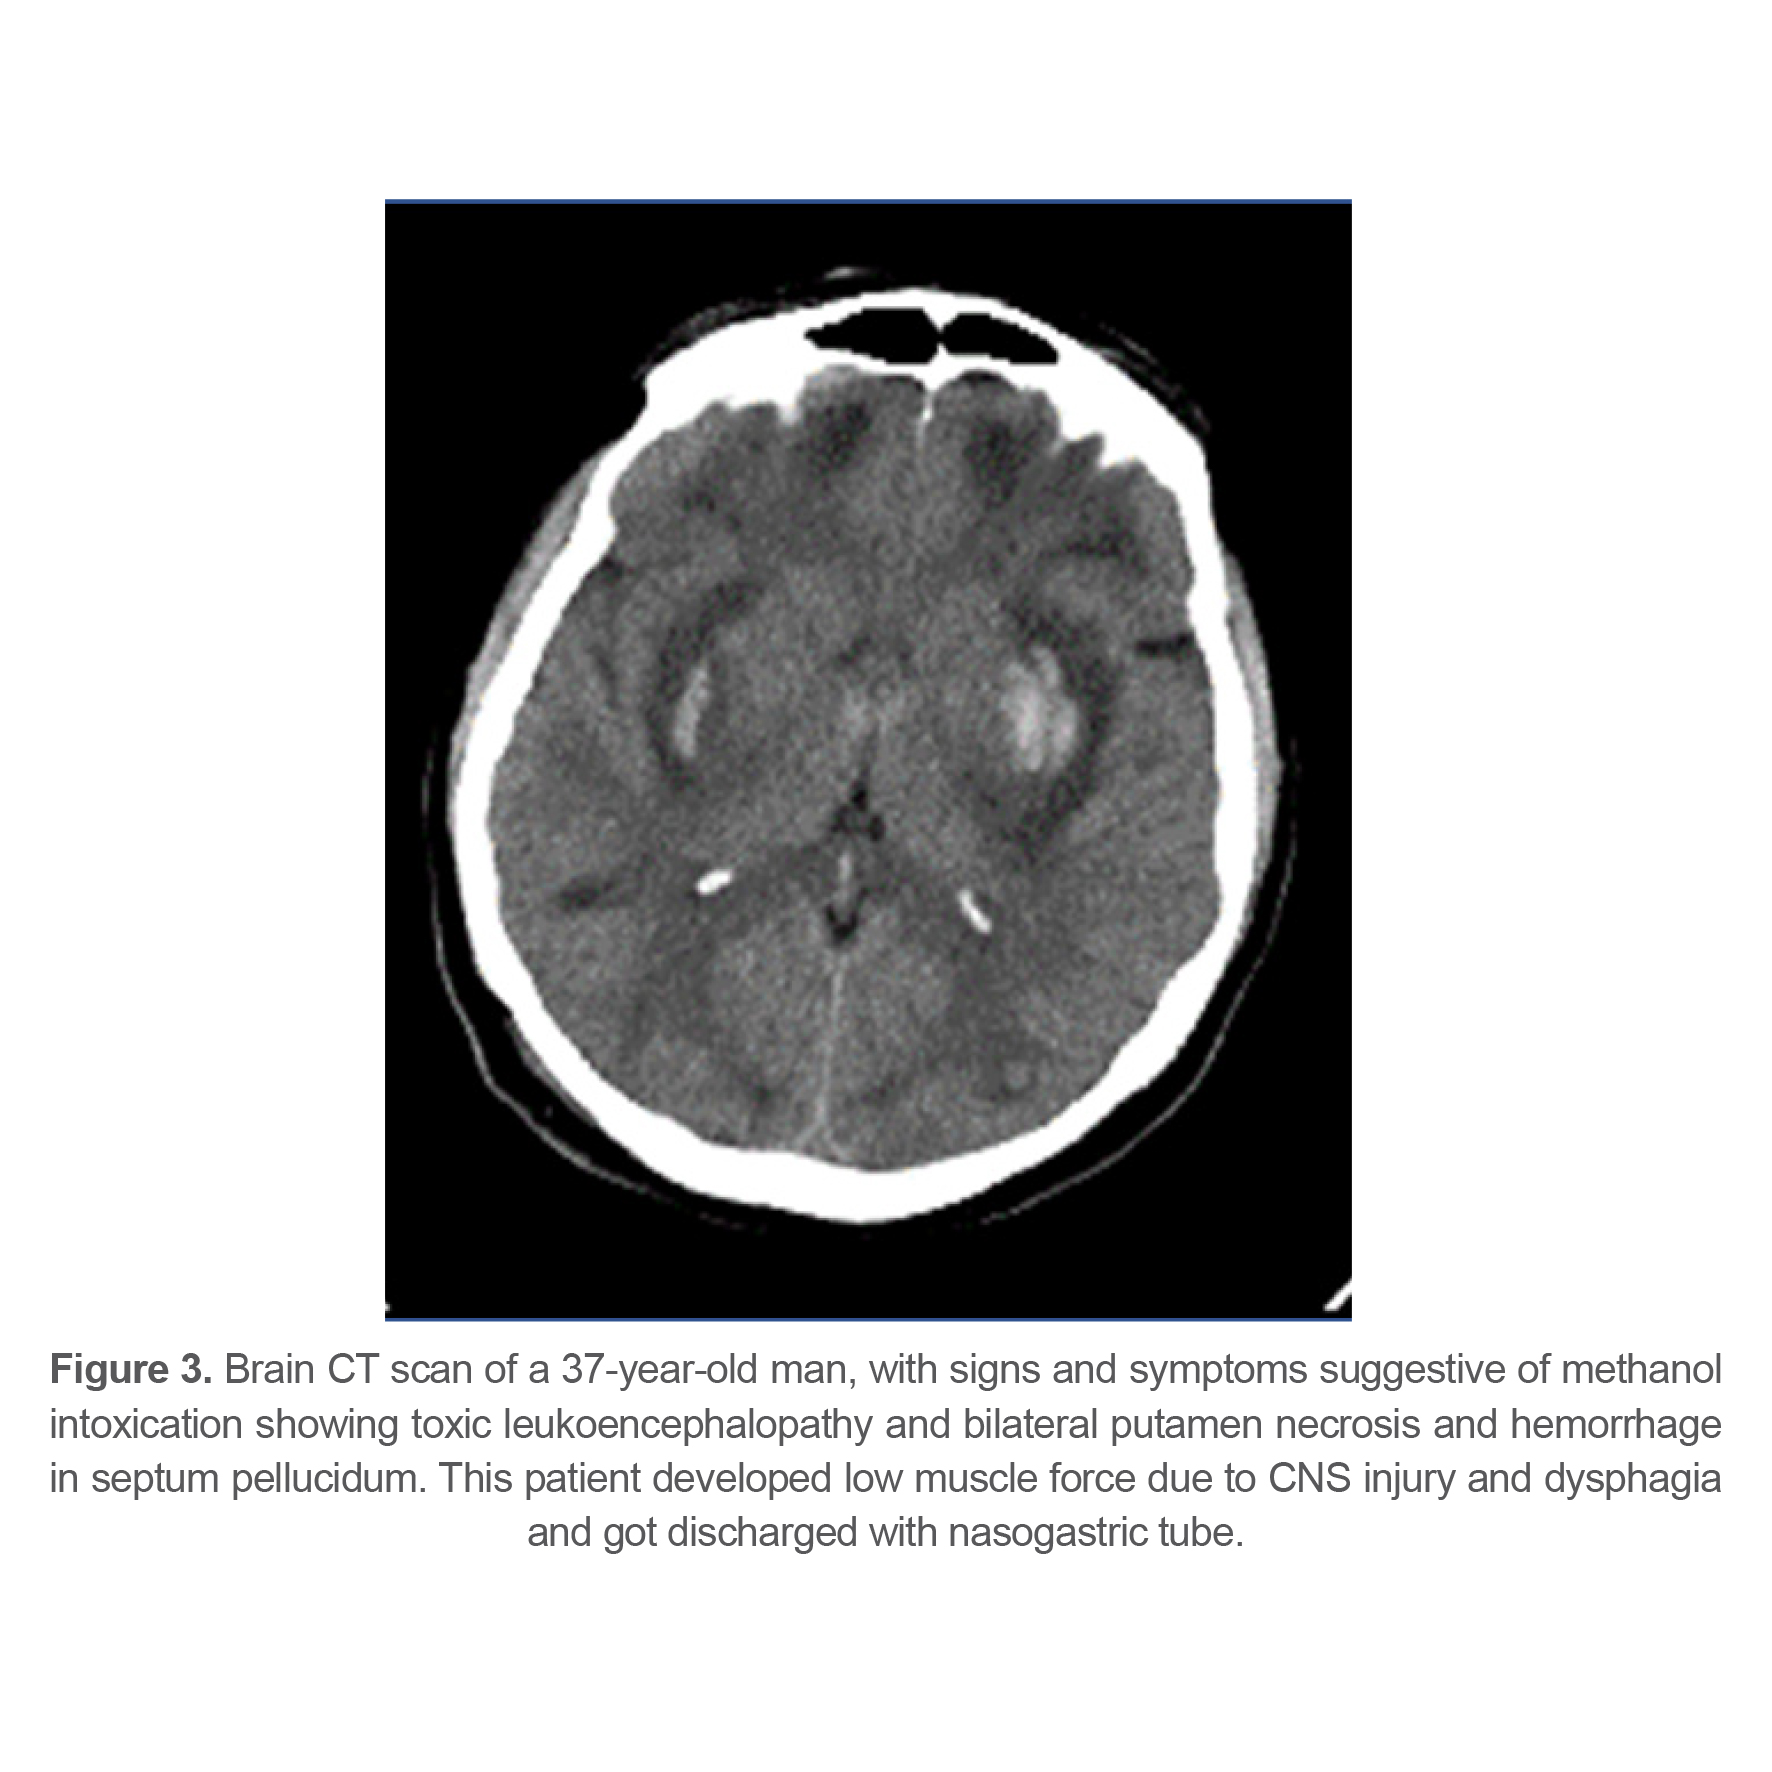

At last, 143 patients (77.72%) recovered completely, 27 patients (14.67%) had sequels at time of discharge from hospital and 14 patients (7.61%) died from methanol poisoning. Different types of complications and their frequency are listed in table 3. 21 patients (11.4%) had some sort of ophthalmologic complications at the time of discharge indicating that ophthalmologic complications were the most common complication among survivors. Figures 1-4 show brain CT scan of 4 patients with brain complications.

Figure 3. Brain CT scan of a 37-year-old man, with signs and symptoms suggestive of methanol intoxication showing toxic leukoencephalopathy and bilateral putamen necrosis and hemorrhage in septum pellucidum. This patient developed low muscle force due to CNS injury and dysphagia and got discharged with nasogastric tube.